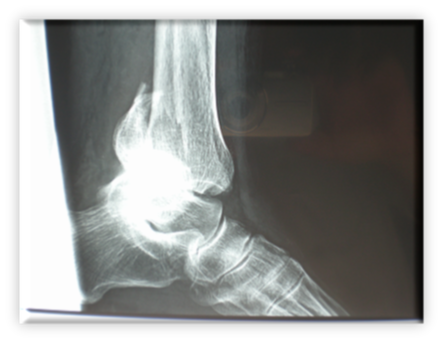

Πρόκειται για αρκετά σοβαρό τραυματισμό, αφού το κάταγμα επεκτείνεται στην άρθρωση (ενδαρθρικό) με συνέπεια αυξημένα ποσοστά μετατραυματικής αρθρίτιδας της ποδοκνημικής. Αυτό καθιστά την ακριβή ανάταξη της αρθρικής επιφάνειας επιβεβλημένη. Ειδικότερα, αν το κάταγμα οπισθίου σφυρού περιλαμβάνει το 1/3 ή περισσότερο της αρθρικής επιφάνειας πρέπει να αναταχθεί και οστεοσυνθεθεί. Τα συνυπάρχοντα κατάγματα του κάτω πέρατος της περόνης (έξω σφυρό) και κάτω έσω πέρας της κνήμης (έσω σφυρό) καθιστούν την άρθρωση  εξαιρετικά ασταθή. Η όλη κατάσταση μπορεί να παρομοιαστεί με ένα τρίποδα του οποίου έχουν σπάσει και τα τρία πόδια. Φτιάχνοντας το ένα ή τα δύο μόνο πόδια, δεν μπορεί να έχει ισορροπία ο τρίποδας, οπότε πέφτει. Αντίστοιχα είναι τα πράγματα και για την άρθρωση της ποδοκνημικής που είναι μια στηρικτική άρθρωση.

Η θεραπεία είναι χειρουργική.